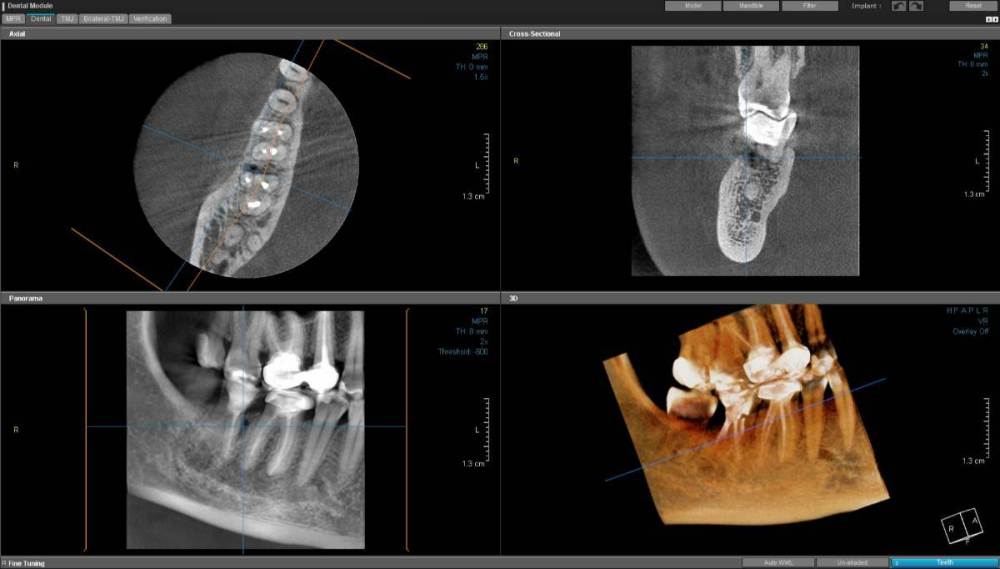

Еврейка Опубликовано 30 января, 2023 Поделиться Опубликовано 30 января, 2023 Добрый день. в апреле 2022 г установила коронку на зуб 46 перед этим прошла подготовку ( поставили штифт) . в июне 2022 г между 47 и 46 зубами на десне обнаружился свищ. все лето и осень выясняли откуда свищ, перелечили каналы на 47 зубе. свищ то исчезал то появлялся. В ноябре 2022 врач назначил пропить доксициклин . свищ исчез но я переболела гриппом в конце 2022 и он опять проявился. в январе 2023 г сделала КЛКТ https://disk.yandex.lv/d/ZXTOp24oEgl5Fg на нем мой врач увидела кариес на 47 зубе ( между 47 и 46 зубом ) , перелечили его , но через неделю опять напухла десна, вскрылся свищ и появилось гнойное отделяемое. сейчас врач предлагает сделать посев из свища и пропить антибиотики согласно посеву. насколько оправдана такая тактика ? если кто сможет посоветовать к кому можно обратиться в кемеровской, новосибирской областях за грамотной диагностиках - прошу написать мне Ссылка на комментарий

wladdX Опубликовано 1 февраля, 2023 Поделиться Опубликовано 1 февраля, 2023 В 8,5 Мб нет снимка(-ов). Собственно, он нужен для понимания динамики процесса (лучше, хуже или без изменений). По состоянию на 11.01.2023 имеется очаг разрежения костной ткани 2х4х6 мм вдоль передней поверхности переднего(медиального) корня и неявные признаки перфорации корня (очень неявные, полной уверенности нет). Нужно, чтоб КТ посмотрел эндодонтист (именно КТ полностью, скриншотов недостаточно). По моему мнению, необходимо удаление зуба 47. На истину в последней инстанции не претендую. 1 Ссылка на комментарий